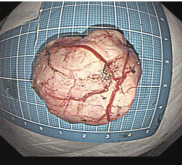

胃内4x4cm粘膜下隆起,胃镜下完整切除(ESE),术后病理证实平滑肌瘤,保留胃正常组织结构。